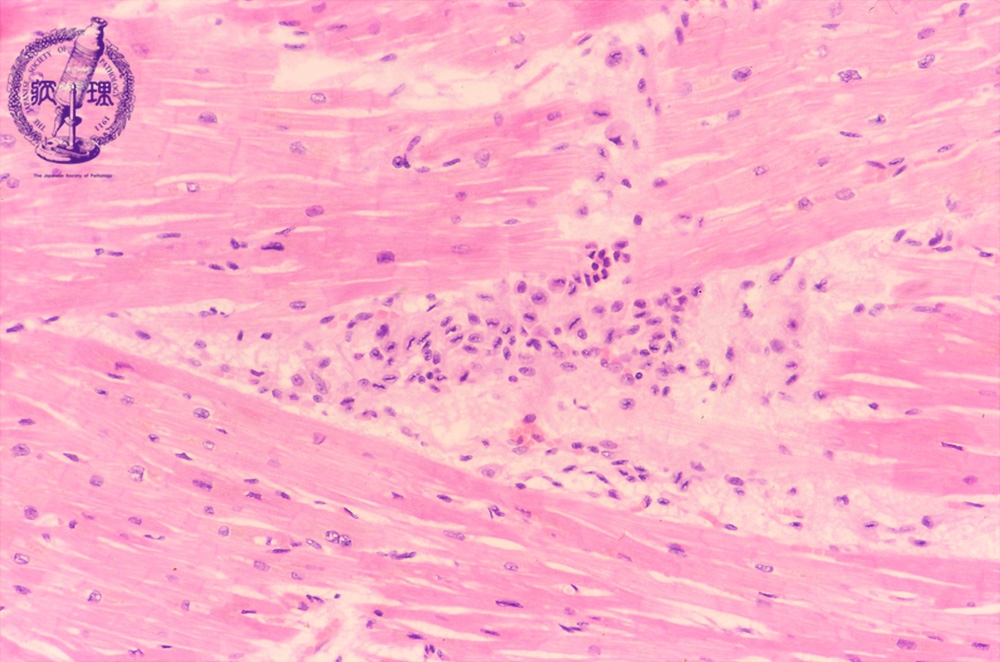

- ★(5)Valvular disease (acute rheumatic fever)

Microscopic image (HE, low power view): The so-called Aschoff nodule, which is a classic finding in rheumatic fever, comprises a nodular inflammatory cell infiltrate within the myocardium and is composed of T cells and activated macrophages.